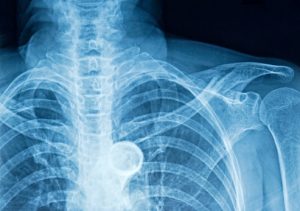

Anteroposterior (AP) and lateral chest X-ray: Great for looking at the structure of the rib cage and routinely assisting in diagnosis and ruling out fractures. Several underlying injuries can also be ruled out with this test, such as hemothorax, pneumothorax, lung contusion, atelectasis, pneumonia, and vascular injuries.